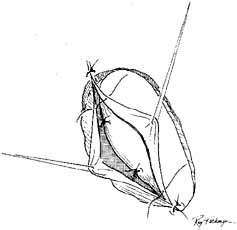

in this area could damage the common canaliculus.  Fig. 35 A and B. Balloon catheter in use as well as endoscopic view in the inferior meatus

of the inflated balloon. Fig. 35 A and B. Balloon catheter in use as well as endoscopic view in the inferior meatus

of the inflated balloon.